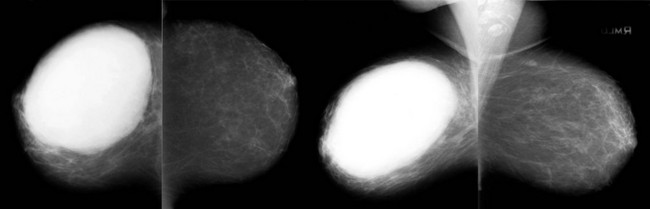

When the tumor is very large, the breast affected with ILC can appear to be getting smaller on mammography—the “shrinking breast” (Fig. 11-3). This is not due to the breast becoming physically smaller, but to the decreased compressibility of the breast tissue that is full of webs of cancer cells. If the contralateral breast compresses to a thickness of 5 cm, a breast with extensive ILC may only compress to 8 cm. Although this results in the appearance of a smaller breast on mammography, breast size is typically symmetric on clinical examination.

FIGURE 11-3 Shrinking Breast.

A 52-year-old woman noted thickening in her left breast. On clinical examination, the breasts are symmetric in size but the texture of the left breast is diffusely thickened. On mammography, the left breast appears to be smaller than the right. Biopsy showed ILC. Did you also notice the one-view asymmetry in the right medial breast? US of this area shows a small hypoechoic mass. Biopsy of the right breast showed IDC.